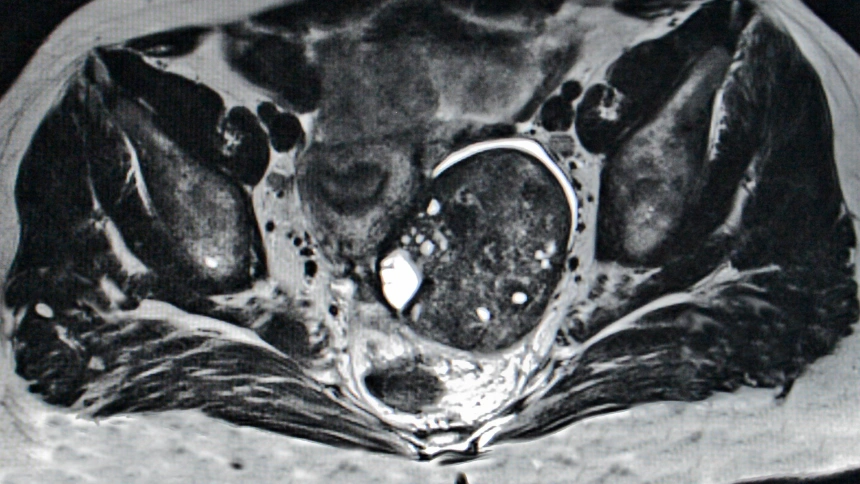

Imagen de recurso

Unos populares medicamentos para reducir el colesterol, y por ende, las enfermedades cardiovasculares, podrían tener un papel muy importante en una mayor supervivencia libre de cáncer de ovario en las pacientes con la enfermedad en estado avanzado.

Los resultados del estudio se han publicado en la revista Cancer Research Communications y sugieren, por primera vez, que la interacción entre las estatinas, fármaco para regular el colesterol, y el niraparib, medicamento para el tratamiento del cáncer de ovario, tiene efectos positivos sobre estas pacientes y, por ende, aumenta significativamente el porcentaje de supervivencia de la enfermedad.